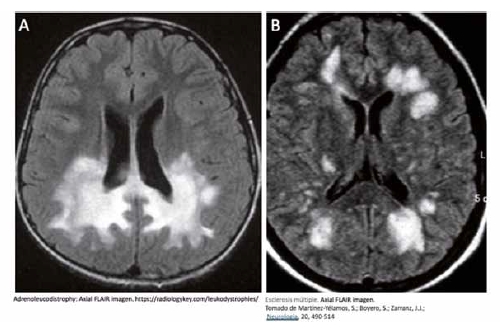

Las leucodistrofias, son un conjunto enfermedades asociadas a mutaciones de proteínas fundamentales para el metabolismo celular de los lípidos. La alteración genética afecta a todas las células del organismo, pero las células productoras de mielina, los oligodendrocitos en el sistema nervioso central, son las que degeneran, asociándose generalmente a un proceso neuroinflamatorio de curso progresivo sin posibilidad de tratamiento (Fig 1.A). Hay formas diversas de presentación dependientes del problema genético asociado, pero en general son progresivas y las formas más severas conllevan la muerte de los pacientes en la infancia [1].

En las enfermedades desmielinizantes adquiridas como la esclerosis múltiple (EM), el sistema inmune reacciona de forma anómala ante estímulos externos (tóxicos, infecciones virales, etc.) produciendo auto-anticuerpos contra la mielina y favoreciendo que las células inflamatorias infiltren el parénquima cerebral para generar un microambiente tóxico. La mielina es la diana selectiva de este proceso y, como consecuencia de la perdida de la vaina de mielina de los axones se produce una alteración severa de la transmisión del impulso nervioso y una degeneración (Fig. 1B) [2].